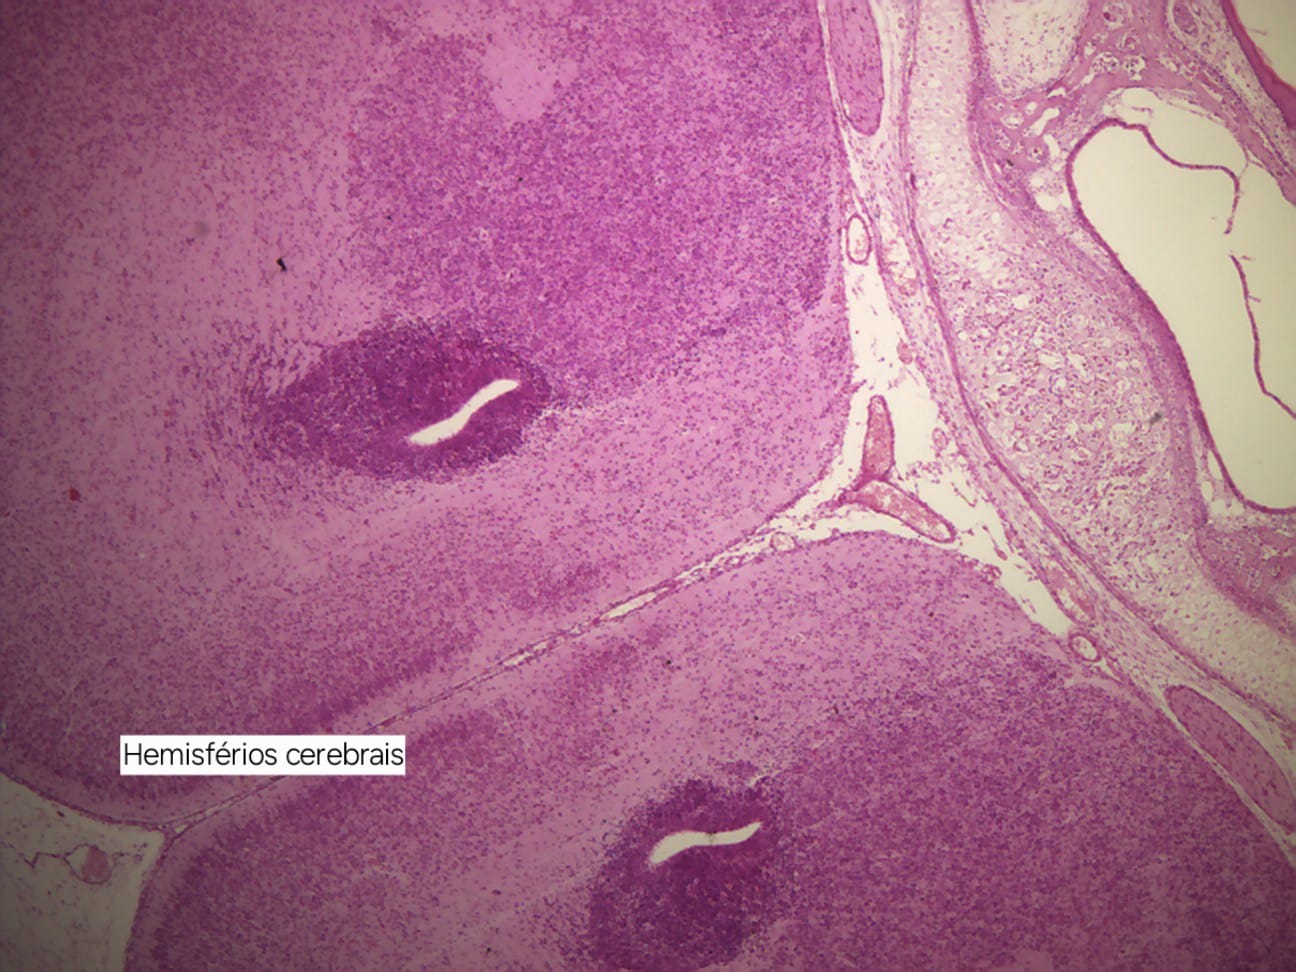

Imagens Embriologia da Face